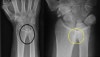

X-ray : DRUJ Arthritis